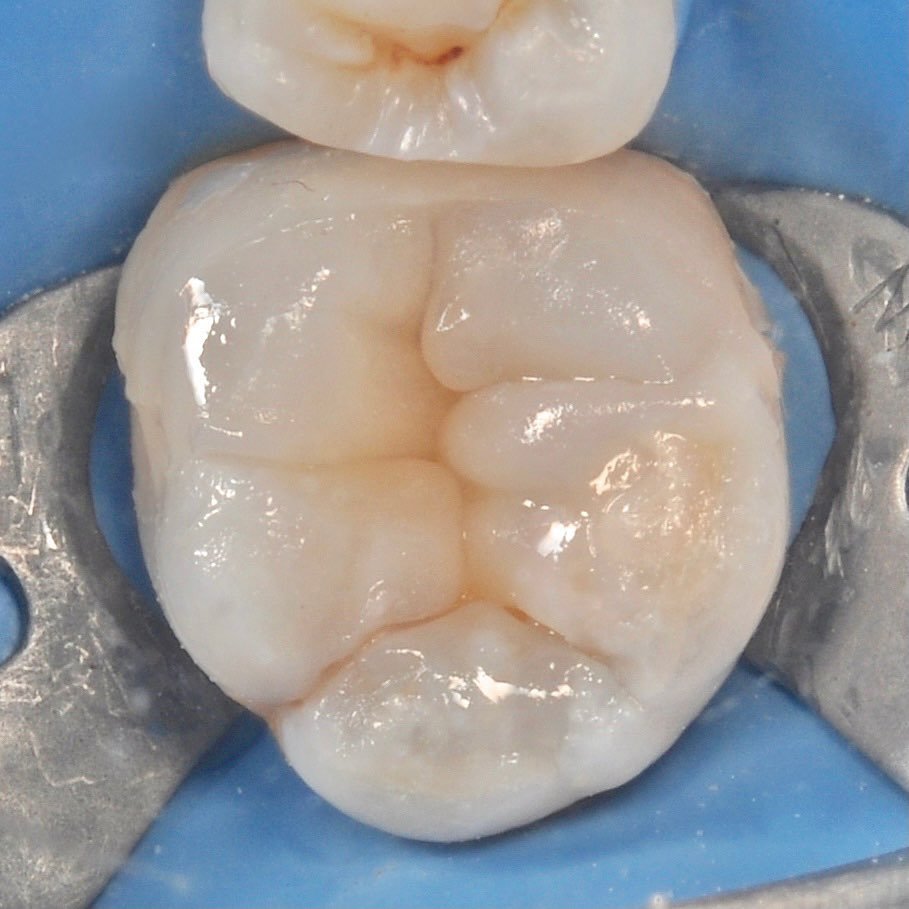

The use of a microscope in dentistry is an ultra-modern direction. Optical instruments allow for constant monitoring of the treatment process, which directly affects the quality of treatment and is aimed at preserving tooth tissues.

The microscope illuminates and enlarges the working field by about 25 times, which helps to accurately determine the anatomical structure of the tooth and restore it with maximum accuracy.

Dental treatment under a microscope

Multiple increase

careful treatment of canals

strengthening the tooth with fiberglass

we install a crown on the cured tooth